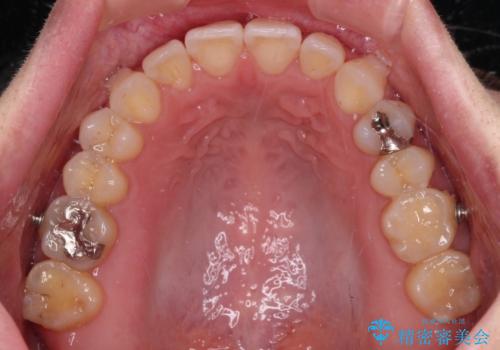

【モニター】狭い上顎歯列とオープンバイト 急速拡大装置を用いた矯正治療

- 前歯の開咬を気にして来院された患者様です。

上顎歯列が狭窄していたため、急速拡大装置により上顎骨を側方に拡大し、その後インビザラインにて矯正治療を行うこととしました。

舌の突出癖が開咬の原因であったので、改善のための舌トレーニングを行っていただきました。

舌トレーニングは後戻りにも大きく影響するため、とても重要なトレーニングです。